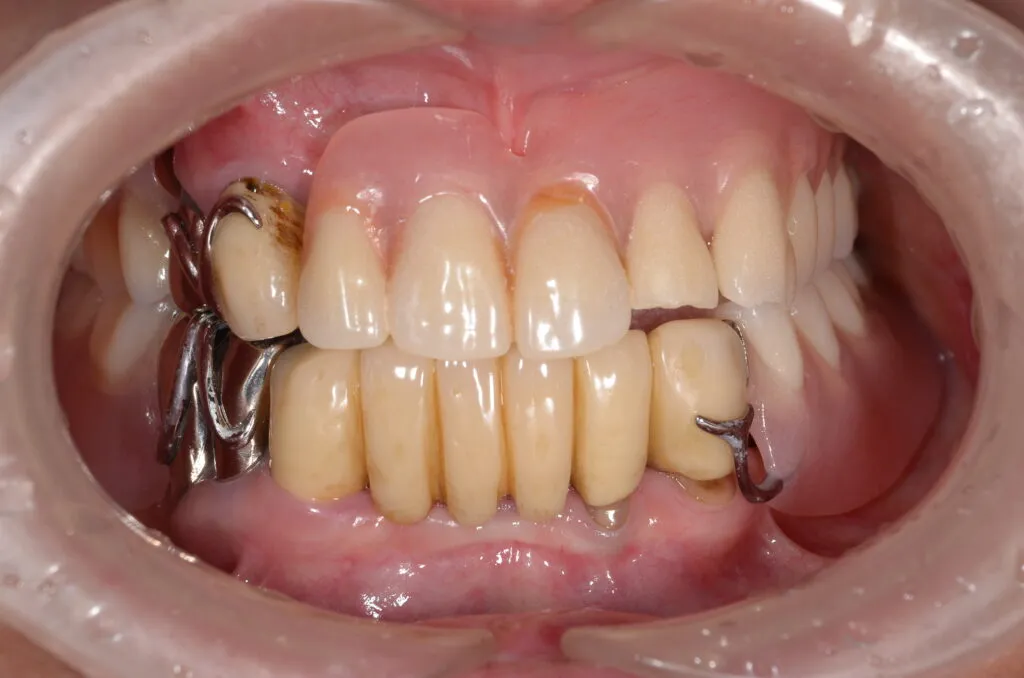

こちらの患者様の場合

【期間】2ヶ月

【費用】¥350,000~¥400,000/片顎(税抜)

【デメリット】精密に製作するため、保険の入れ歯よりも回数・費用がかかります。

上記写真は当院で上下総義歯を作製した患者さんです